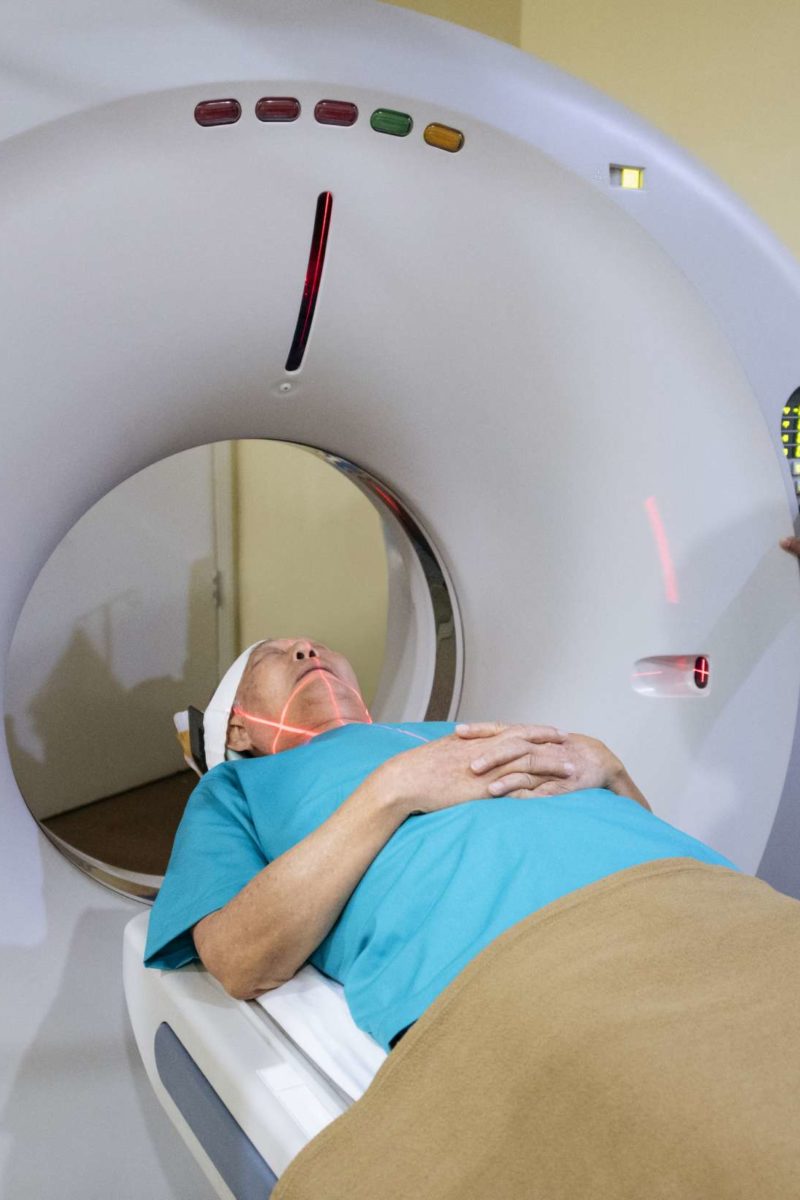

CT For Kids: What Is A CT Scan? | UVA Radiology Blog

blog.radiology.virginia.edu

blog.radiology.virginia.edu

ct scan kids medical machine scanner radiology head picture equipment imaging children hospital definition division